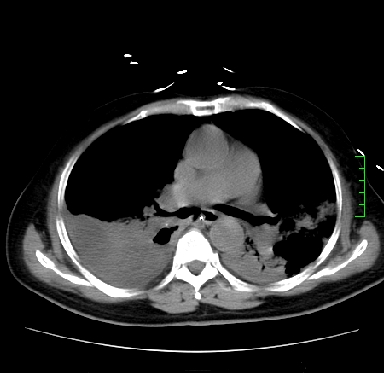

icu病人,几天都没明确诊断。m,76y,咳嗽、咳痰1周,伴气促,右胸痛入院,pe:t38.3c p135 r25 bp135/85。双肺可闻及大量湿罗音,心、腹未见明显异常。诊断:1心衰?2肺部感染?3冠心病?

11号ct

1)两肺感染性病变(右肺下叶肺脓肿可能)。2)双侧胸腔积液,以右侧为甚。

ards,肺感染性病变,右下叶实变,双侧胸腔积液,右侧为著,叶间胸膜积液,右上肺陈旧性tb纤维灶,左室大。

考虑:双肺感染、右肺下叶肺脓肿,双侧胸腔积液,肺水肿.请结合临床.